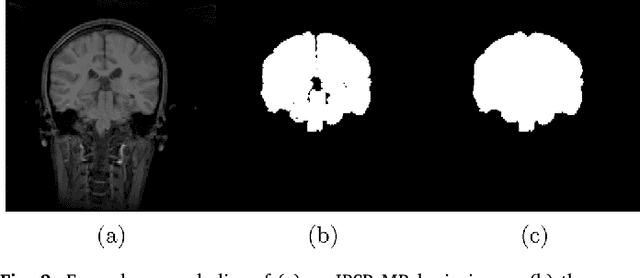

Abstract:Brain extraction from images is a common pre-processing step. Many approaches exist, but they are frequently only designed to perform brain extraction from images without strong pathologies. Extracting the brain from images with strong pathologies, for example, the presence of a tumor or of a traumatic brain injury, is challenging. In such cases, tissue appearance may deviate from normal tissue and violates algorithmic assumptions for these approaches; hence, the brain may not be correctly extracted. This paper proposes a brain extraction approach which can explicitly account for pathologies by jointly modeling normal tissue and pathologies. Specifically, our model uses a three-part image decomposition: (1) normal tissue appearance is captured by principal component analysis, (2) pathologies are captured via a total variation term, and (3) non-brain tissue is captured by a sparse term. Decomposition and image registration steps are alternated to allow statistical modeling in a fixed atlas space. As a beneficial side effect, the model allows for the identification of potential pathologies and the reconstruction of a quasi-normal image in atlas space. We demonstrate the effectiveness of our method on four datasets: the IBSR and LPBA40 datasets which show normal images, the BRATS dataset containing images with brain tumors and a dataset containing clinical TBI images. We compare the performance with other popular models: ROBEX, BEaST, MASS, BET, BSE and a recently proposed deep learning approach. Our model performs better than these competing methods on all four datasets. Specifically, our model achieves the best median (97.11) and mean (96.88) Dice scores over all datasets. The two best performing competitors, ROBEX and MASS, achieve scores of 96.23/95.62 and 96.67/94.25 respectively. Hence, our approach is an effective method for high quality brain extraction on a wide variety of images.